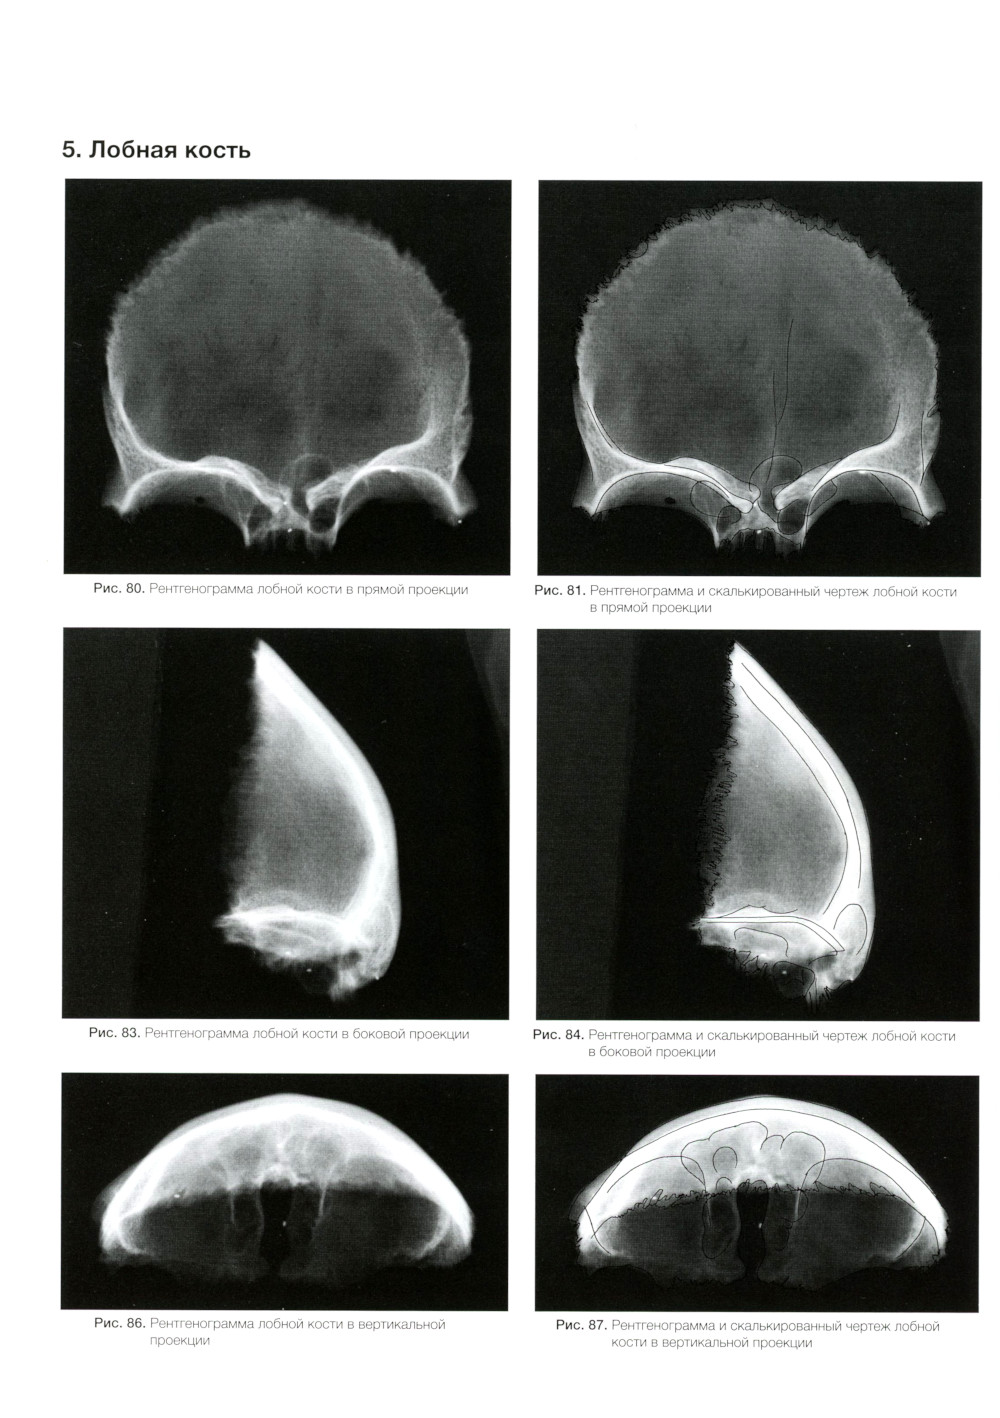

Аннотация: Атлас рентгенологической цефалометрии

Эта книга является дополненным и усовершенствованным вариантом «Атласа рентгенологической анатомии и цефалометрии», вышедшего в свет в 1986 г. только на японском языке и ставшего весомым подспорьем практикующим специалистам и ординаторам, а также студентам.| Издательство | Азбука стоматолога |

Атлас рентгенологической цефалометрии